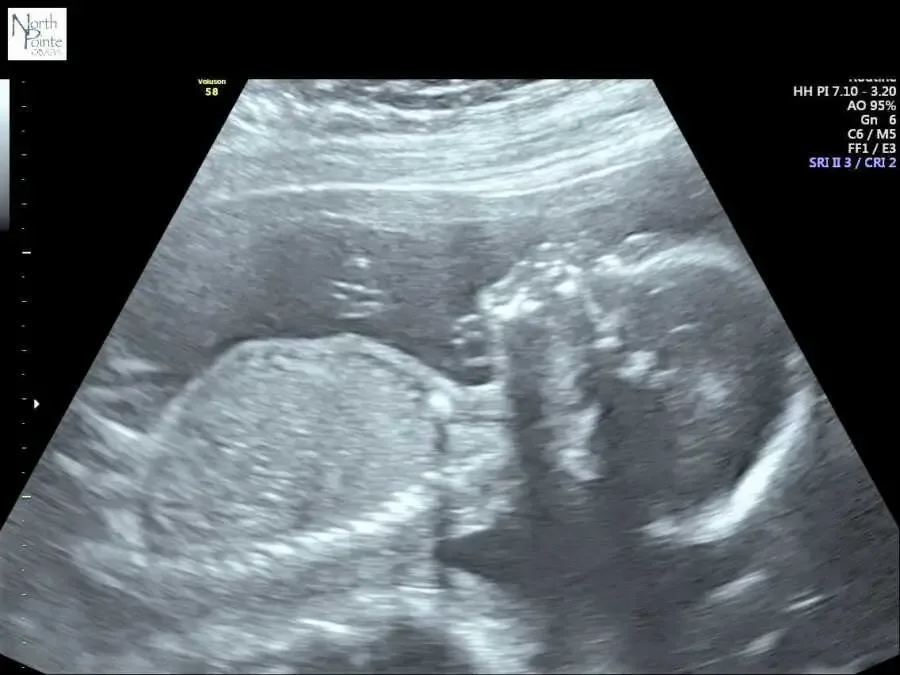

Despite losing one ovary, my husband and I decided to try for a family. On St. Patrick’s Day 2019, we welcomed our son, Maximilian. A few years later, we were blessed again with our daughter, Madelyn. With only one ovary, I joke that I truly put all my eggs in one basket, but both children are miracles.